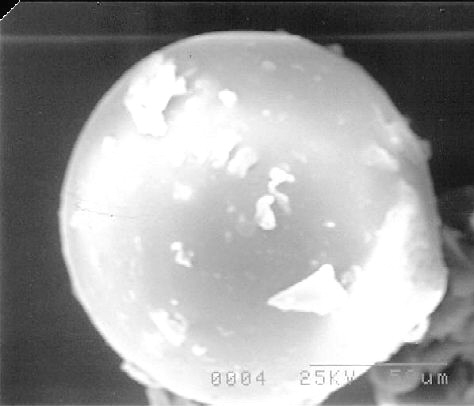

External Morphology, Particle Size and Size distribution

Gross morphology at 25 X magnification was studied by mounting the microparticles on clean glass slides and observing via light optical microscope for particle shape, clumping etc. SEM samples were coated with gold for 90 seconds under an argon atmosphere using a Polaron E 5100 coater at room temperature. A Jeol model 35 (Jeol, Peabody, MA) operated at a voltage of 25Kv and a working distance of 50 mm at an angle of 40° under 100 X and 300 X magnification (600 X for the final selected sample) was used to visualize the samples. Sieve analysis was used to estimate the geometric mean weight diameter (d') and the geometric standard deviation (s) as well as particle size distribution. 10, 40, 60, 100 and 140 mesh sieves were arranged with sieve 10 at the top, and sieve 140 at the bottom. A weighed sample was placed on the top sieve, shaken for 30 minutes, and the cumulative percent by weight of the powder retained on the sieve was plotted on the probability scale against the logarithm of the arithmetic mean sizes of two successive screens. The geometric mean weight diameter (d') was directly obtained from the graph by taking antilog of the 50% size while the geometric standard deviation (s) was calculated from the expression

In Table 3, speeds below 2000 rpm presented large, irregularly shaped particles (Figures 9) while speeds above 8000 rpm (Figures 10) yielded brown-tinted dispersions interpreted as visible signs of degradation.

SEMs of products processed between 4000 and 8000 rpm displayed uniform spheres and this range was selected for further investigation in the design of the experiment discussed earlier.

Figure 9: SEM (100x) showing effect of homogenizer speed 8000 rpm.

Figure 10: SEM (100x) showing effect of homogenizer speed 2000 rpm.

Figure 11: SEM of Lot 19 at 100 x.

Figure 12: SEM of Lot 19 at 600 x.

Figure 13: SEM of Lot 8 at 100 x.

Figure 14: SEM of Lot 8 at 300 x.

Figure 15: SEM of Lot 13 at 100 x.

The scanning electron micrographs of the representative samples are shown in Figures 11-16.

Figure 16: SEM of Lot 13 at 300 x.

Microparticles from the selected batch exhibited spherical morphology and smooth surface.

The geometric mean weight diameter was 195 ± 1.54 m for samples from Lot 6, 190 ± 1.28 mm for samples from Lot 13 and 195 ± 1.28 m from the final selected Lot 19 sample. The size and size distribution graphs for representative samples are shown in Figures 17 and 18.